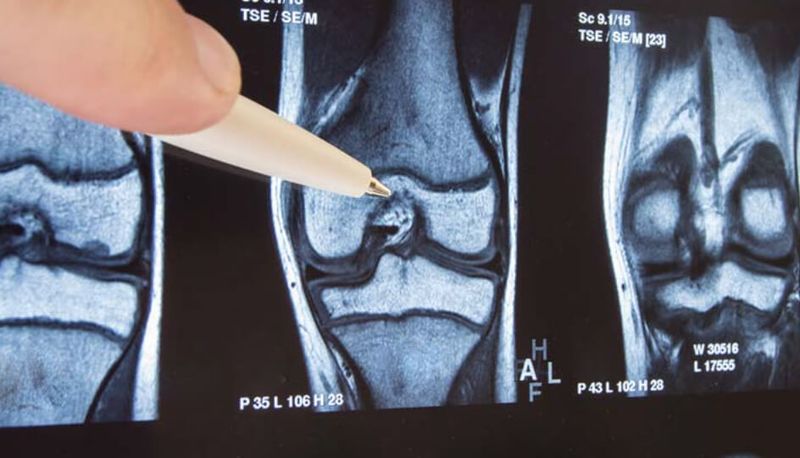

MRI-onderzoeken aan het begin van het onderzoek en na een periode van vier jaar toonden niet alleen een voordeel van de pijnstillers op de lange termijn.

Toen de onderzoeksleider Dr. Johanna Luitjens van de Universiteit van Zürich in Bazel (Zwitserland) de onderzoeksresultaten presenteerde op de jaarlijkse bijeenkomst van de Radiological Society of Europe, zat ik voor het scherm en volgde de presentatie via livestream.